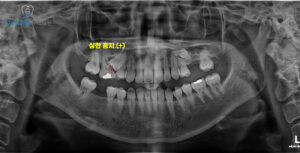

이렇게 어느정도의 잇몸이 회복된 후

임플란트 식립을 진행했어요.

먼저 잇몸뼈의 가장 위쪽인

치조정 부위로 접근하여,

상악동 안쪽에 있는 얇은 막을

조심스럽게 들어 올리는

상악동 거상술을 시행했답니다.

이 과정을 통해 임플란트를

심을 수 있는 공간을 확보한 뒤,

충분한 지지력을 얻을 수 있도록

임플란트를 안정적으로 식립했어요.

더불어 잇몸뼈가 부족한 부위에는

뼈이식을 함께 진행하여,

임플란트 주변을

단단하게 보강해 주었어요.